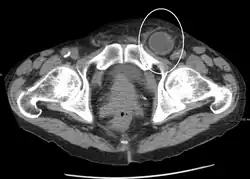

Medical imaging

A physician may diagnose an inguinal hernia, as well as the type, from medical history and physical examination.[20] For confirmation or in uncertain cases, medical ultrasonography is the first choice of imaging, because it can both detect the hernia and evaluate its changes with for example pressure, standing and Valsalva maneuver.[21]

When assessed by ultrasound or cross sectional imaging with CT or MRI, the major differential in diagnosing indirect inguinal hernias is differentiation from spermatic cord lipomas, as both can contain only fat and extend along the inguinal canal into the scrotum.[22]

On axial CT, lipomas originate inferior or lateral to the cord, and are located inside the cremaster muscle, while inguinal hernias lie anteromedial to the cord and are not intramuscular. Large lipomas may appear nearly indistinguishable as the fat engulfs anatomic boundaries, but they do not change position with coughing or straining.[22]